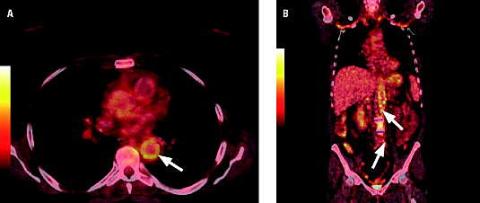

A. Positronemissionstomografi/computertomografi, tværsnitsbillede hvor der ses opladning i aortas væg.

B. Positronemissionstomografi/computertomografi, koronalsnit hvor der ses opladning i aa. subclaviae, aorta samt overgangen til aa. iliacae communis.

Generne havde på det tidspunkt stået på i en måned. Patientens symptomer var træthed, fryseture, smerter i yderled på alle fingre og mavesmerter, der var lokaliseret til epigastriet og var værst efter måltider. Desuden havde hun haft et utilsigtet vægttab på 10 kg. Objektivt blev hun fundet febril med en temperatur på 38,3 °C, gusten i hudkuløren, hævede distale/proksimale led og palpatorisk ømhed i epigastriet. Paraklinisk var der forhøjelse af C-reaktivt protein til 198 mg/l og sænkningsreaktion på 98 arbitrære enheder. Som led i udredningen blev der foretaget positronemissionstomografi/computertomografi (PET/CT), der viste en opladning i væggen af aortas forløb fra aortaklap til iliacakar og aa. subclaviae. På mistanke om storkarsvaskulitis blev der foretaget en arteria temporalis-biopsi, der viste histologisk kæmpecellearteritis.

PET/CT er et værktøj, som kan give mistanke om diagnosen, og denne kan i 60% af tilfældene bekræftes ved a. temporalis-biopsi [3, 4].